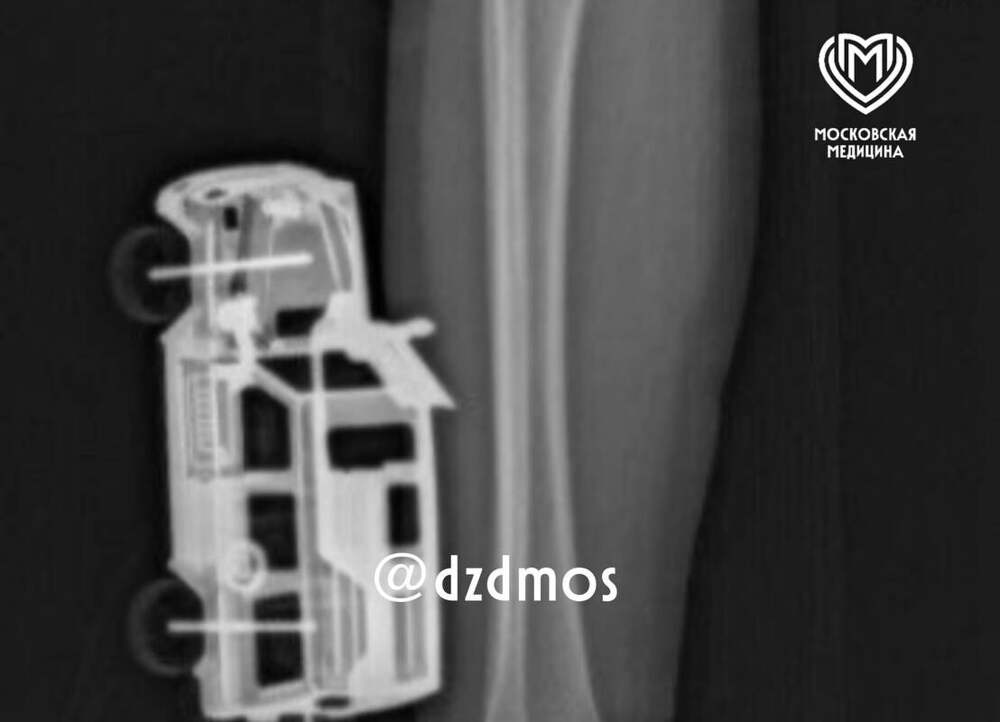

В Москве врачи спасли мальчика с игрушечной машинкой в ноге

В Москве четырехлетний мальчик упал на игрушечную машинку и оказался в больнице. Об этом сообщает Telegram-канал "Московская медицина". По словам родителей, ребенок прыгнул с кровати у себя дома и неудачно упал на игрушку правой голенью. Машинка повредила мягкие ткани, ее части вошли глубоко и